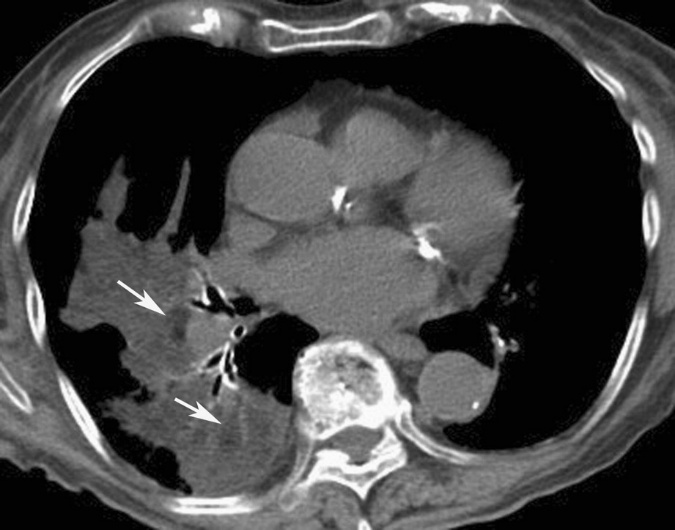

LP最具诊断意义的CT表现是肺实变区域内存在负值衰减区(脂肪密度灶)(图7)。实际测量值往往高于纯油,这是因为油脂在受累肺实质中扩散并与肺纤维化和/或炎性渗出物混合所致。其他物质误吸,虽可产生类似类脂性肺炎的肺实变,但不会出现脂肪密度区特征。

图7 下肺层HRCT纵隔窗示右肺下叶实变区内低密度区(CT值-31~-116HU,↘)[1]

实变区域内检测到因脂肪衰减导致的CT值介于-150~-30HU的“低密度区”高度提示肺内脂肪沉积,尤其当患者有油脂接触史时更具诊断价值。

进行CT值测量时需格外谨慎以避免假阳性结果:

测量点应选择实变区最低密度部分;

需避开实变周边含气肺组织或支气管气相区域;

部分容积效应(含气肺组织与软组织平均)可能模拟脂肪特征性CT值。